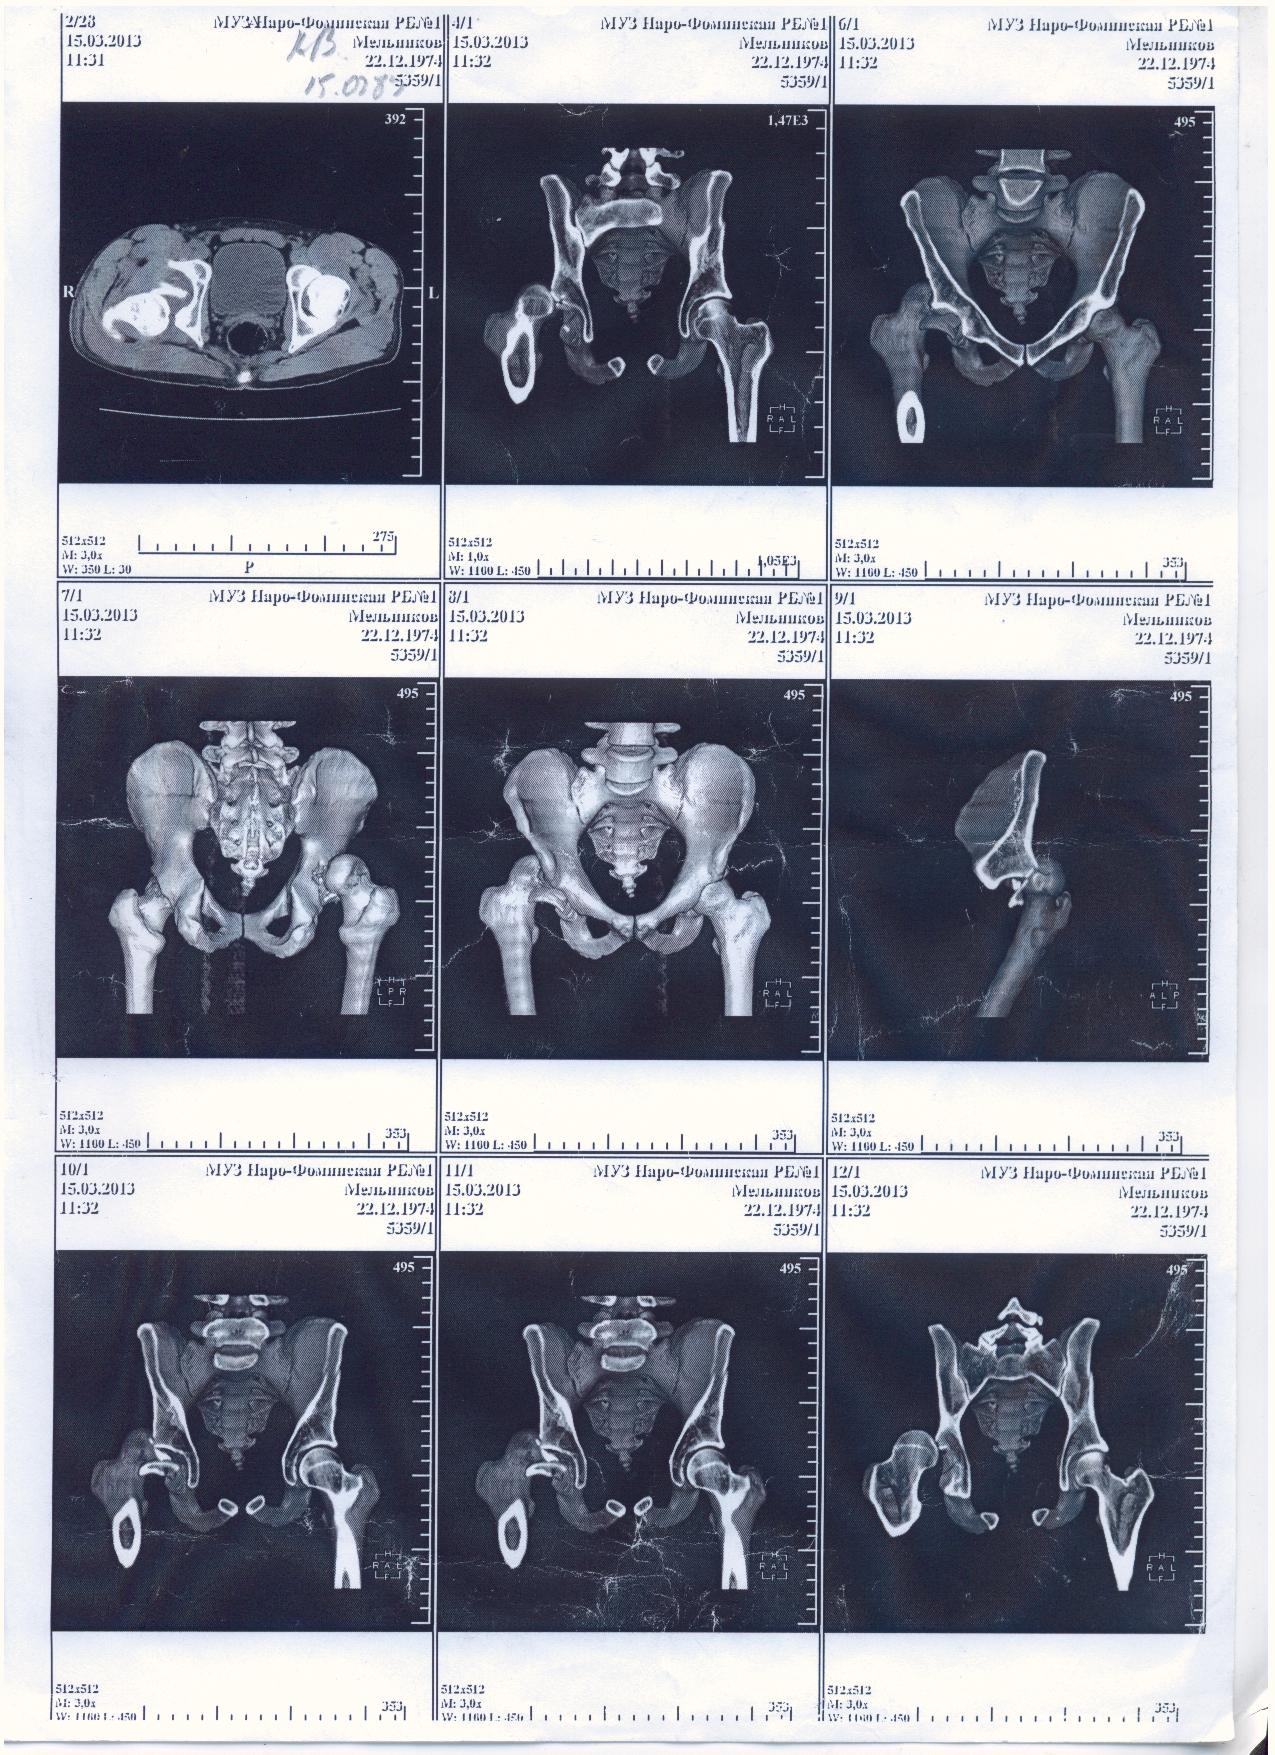

Мой товарищ попал в страшную аварию, виновник аварии как и два его пассажира погибли. Товарищ с пассажиром живы, но другу нужна сложная операция. Мы не можем никак найти врача способного прооперировать бедренный сустав, в пироговке отказали. Парню всего 30 лет всеми силами пытаемся поставить на ноги. выкладываю выписки и документы, могу выслать архивом на почту или привезти куда скажите.